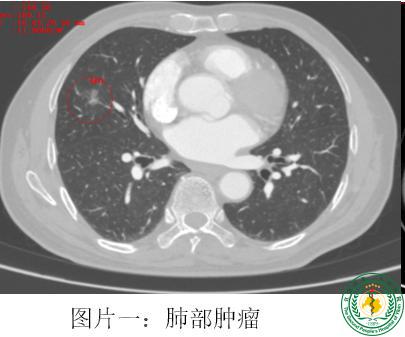

宜宾首例!我院成功开展胸部单操作孔胸腔镜食管癌联合肺癌根治手术

宜宾首例!我院成功开展胸部单操作孔胸腔镜食管癌联合肺癌根治手术57498